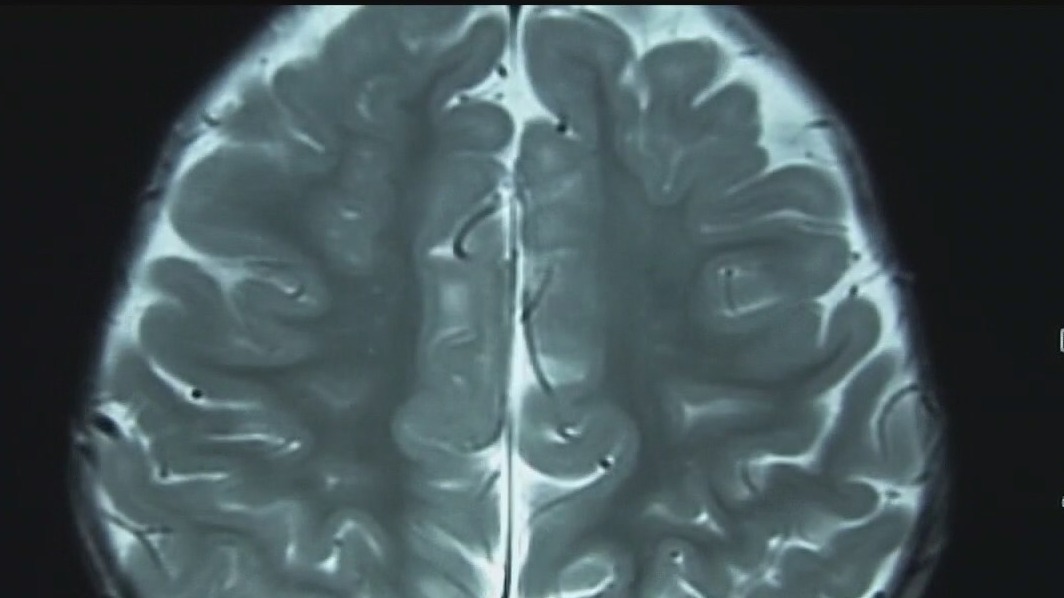

Looking at how pandemic changed our brains

How do we cope with the changes the pandemic has left on our minds? Communication pathologist and neuroscientist Dr. Caroline Leaf has some advice.